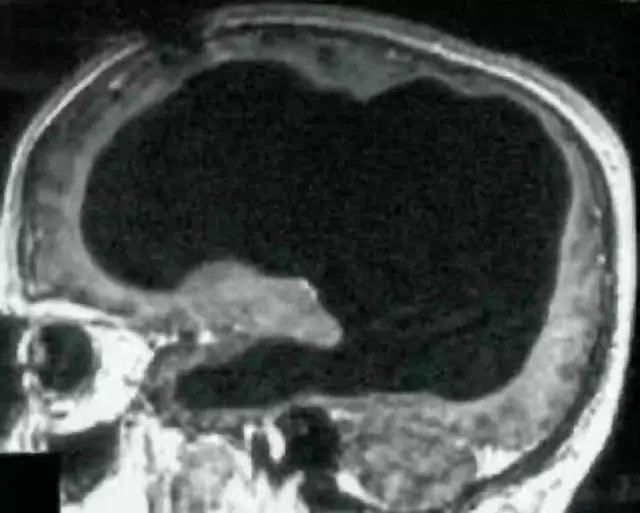

A 44-year-old man in France stunned the medical world when he went to the doctor for a leg ache. After a routine scan, doctors discovered that most of his brain was missing. Instead of brain tissue, his skull was mostly filled with fluid.

The man had a condition called hydrocephalus, often known as “water on the brain.” He was diagnosed as an infant and treated with a tube to drain the fluid. However, the tube was removed when he was 14. Over the next 30 years, the fluid slowly built up and pushed his brain tissue against the walls of his skull.

Despite having very little brain tissue left, the man lived a perfectly normal life. He was married, had a family, and held a steady job. While his IQ was slightly below average, he showed no signs of significant mental impairment.

This case has forced scientists to rethink how the brain works. It suggests that the human brain is much more adaptable than once thought. If parts of the brain are lost slowly over time, other areas can learn to take over their roles.

This discovery challenges the idea that specific parts of the brain are responsible for our consciousness. It shows that even with major physical changes, the mind can find a way to function. The brain’s ability to rewire itself remains one of the greatest mysteries in medicine.